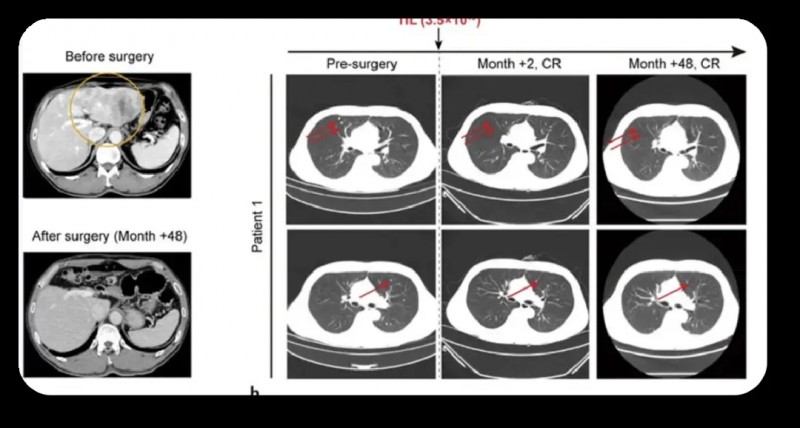

患者1为一例49岁男性,因肝细胞癌破裂入院。上腹部CT示左肝叶多发病灶(最大71×48mm),左侧门静脉癌栓形成;肺部CT检出多发结节,甲胎蛋白(AFP)超60,500ng/mL,确诊为乙型肝炎病毒(HBV)相关性肝细胞癌(BCLCC期)。该患者入组I期临床试验(NCT03658785)后,先接受左半肝切除术,术中获取肿瘤组织用于TIL培养;后续依次接受淋巴细胞清除方案(环磷酰胺+氟达拉滨)、TIL细胞回输、白细胞介素-2(IL-2)治疗及两次托珠单抗注射。

结果显示:肝切除术后2个月,所有肺转移灶完全消退,截至目前随访48个月(4年),患者持续无瘤生存(详见下图a、b)。

▲图源“Liver Cancer”,版权归原作者所有,如无意中侵犯了知识产权,请联系我们删除